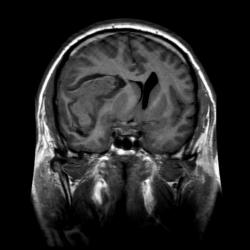

Асимметрия трактов головного мозга в результате их смещения:

В данном случае это классический геморрагический инсульт. По моему опыту с таким смещением срединных структур как на представленных МР-томограммах нейрохируги редко берут на операцию - благополучный постоперационный прогноз маловероятен, да и большиноство пациентов погибают за считанные часы, многие на операционном столе. Евгений, наверное, узнает у пат.анатомов результат вскрытия и напишет нам уже верифицированный диагноз.

Работая совместно с нейрохирургами, которые занимаются сосудистой патологией, перед нами постоянно ставят именно эту задачу: определить причину кровоизлияния, а отсюда и тактику доступа при нейрохирургическом вмешательстве (пункционно идти на ту или иную гематому или открытым доступом или вообще не вмешиваться и вести определенных больных консервативно). Вы правы, что при таком обширном кровоизлиянии МР-ангиография (особенно на 2-3 сутки после начала заболевания) часто оказывается бесполезной, так как из-за зоны кровоизлияния определенная часть сосудов основания мозга просто не визуализируется, или значительно смещена и деформирована именно зона интереса, что увеличивает риск неправильной трактовки данной патологии. Тогда нейрохирургам приходится применять классическую селективную ангиографию (если они действительно подозревают аневризму). Но в данном случае мы видим МР-томограммы и МР-ангиограммы в первые часы гемор.инсульта, поэтому сосуды хорошо получились. А МР-трактография (у нас нет такого оборудования как у Евгения, поэтому мы эту методику не применяем) может тоже помочь планировать операционный доступ и объем оперативного удаления гематомы с учетом видения расположения проводящих путей, их заинтересованности в патологическом процессе с целью минимальных послеоперационных осложнений и неврологического дефицита. Эта методика сейчас актуальна не только для изучения опухолей но и сосудистых заболеваний. С уважением Visus 07

В общем и целом я абсолютно согласен. Прямое показание к трактографии - это планирование операционного доступа.